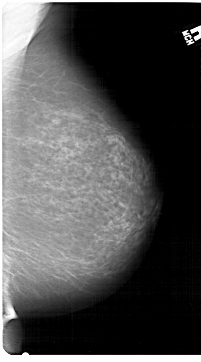

A_1307_1.LEFT_MLO

LEFT_MLO LINES 6751 PIXELS_PER_LINE 4126 BITS_PER_PIXEL 12 RESOLUTION 43.5 OVERLAY